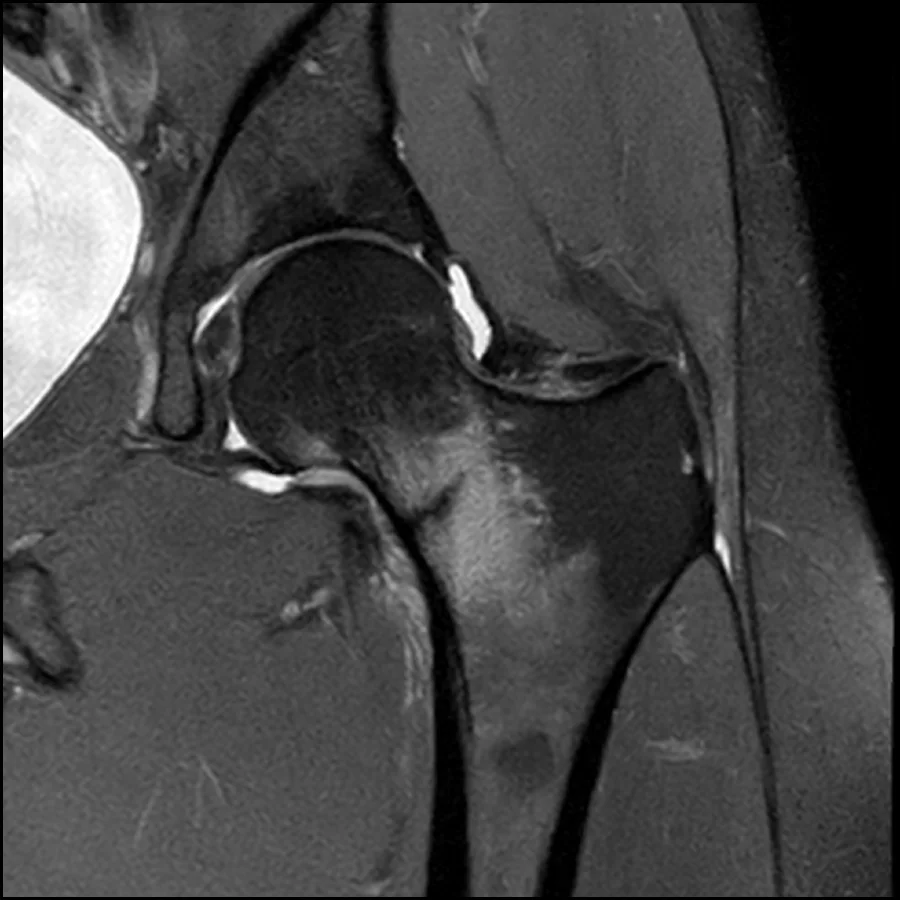

- MRI is the gold standard for early diagnosis, as plain radiographs are frequently normal in early disease.

Because of these limitations, MRI is considered the gold standard for diagnosis. MRI can detect early bone marrow edema, which represents a stress reaction before a visible fracture develops. It also allows direct visualization of a fracture line and enables grading of injury severity, which is crucial for guiding management decisions.

Importantly, MRI findings often change clinical management completely, distinguishing between cases that can be managed conservatively and those requiring urgent surgical intervention. This makes early imaging not only diagnostic but also prognostic in nature, directly influencing return-to-sport outcomes and complication risk.